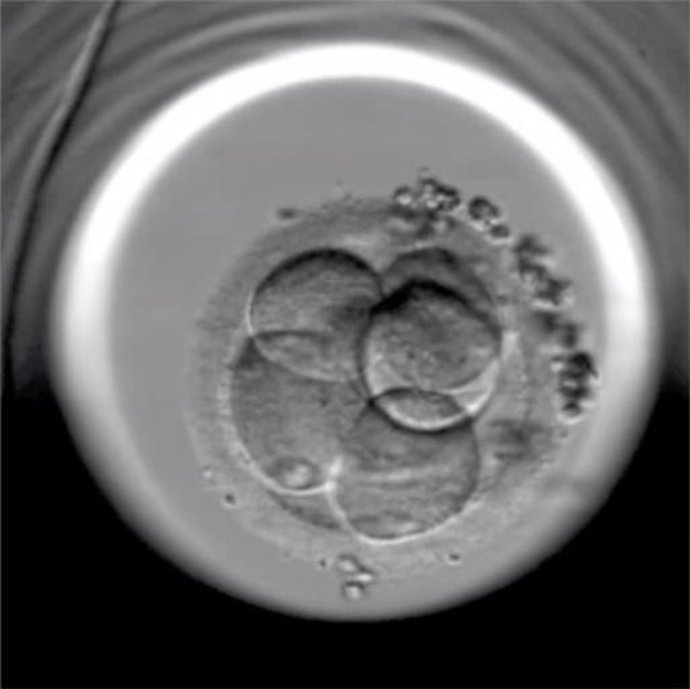

Una nueva incubadora permite observar vía Internet la evolución de embriones fecundados

Embrión Fertilizado Reproducción In Vitro

El Institut Marquès de Barcelona ha incorporado una incubadora de última generación dotada con una cámara de video que permite observar continuamente la evolución de los embriones obtenidos de una fecundación in vitro, también vía Internet.

En un comunicado, el centro médico ha indicado que, gracias a esta técnica, es posible determinar mejor la viabilidad futura de los embriones, lo que ha permitido que se quedara encinta una pareja irlandesa con 15 tratamientos previos fallidos --siete ciclos de inseminación, cuatro ciclos de fecundación in vitro y otros cuatro de donación de óvulos--.

La máquina, conocida como Embryoscope, ha sido presentada con motivo del congreso de la Sociedad Española de la Fertilidad (SEF), que se celebra estos días en Granada.